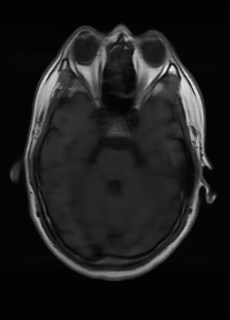

As we observe from the right image in Fig. 2, our BRM, both from MIMO and SISO settings, predicts the performance of dedicated models with a high correlation. We further choose the best three , and perform the last stage of fine-tuning accordingly to (6). A visual evaluation on real data is shown in Fig. 3. For simulated data, please refer to the Supplemental Material section.

Base on the best performing , we perceive that among , , and FLAIR, the results are best when is sampled the most. We suggest that this makes intuitive sense as images provide the best contrast out of the three sequences, which can compensate for the details lost in other images. The same observation can be made on the simulated data, where both and FLAIR show good contrast. When the time setting is changed to non-uniformity, we can see that our search for the best sampling strategy reflects the change. is sampled more as a result of faster acquisition time, while is still sufficiently sampled.

| Sequence | LR | SISO | MIMO | MIMO tuned | GT |

|---|---|---|---|---|---|

(a) 34.38/0.9371

(a) 34.38/0.9371

|

(b) 42.42/0.9883

(b) 42.42/0.9883

|

(c) 44.60/0.9920

(c) 44.60/0.9920

|

(d) 45.50/0.9940

(d) 45.50/0.9940

|

(e) PSNR/SSIM

(e) PSNR/SSIM

|

|

(f) 29.74/0.8903

(f) 29.74/0.8903

|

(g) 36.25/0.9734

(g) 36.25/0.9734

|

(h) 36.42/0.9752

(h) 36.42/0.9752

|

(i) 37.70/0.9832

(i) 37.70/0.9832

|

(j) PSNR/SSIM

(j) PSNR/SSIM

|

|

(k) 39.89/0.9311

(k) 39.89/0.9311

|

(l) 43.94/0.9864

(l) 43.94/0.9864

|

(m) 44.74/0.9883

(m) 44.74/0.9883

|

(n) 45.49/0.9894

(n) 45.49/0.9894

|

(o) PSNR/SSIM

(o) PSNR/SSIM

|